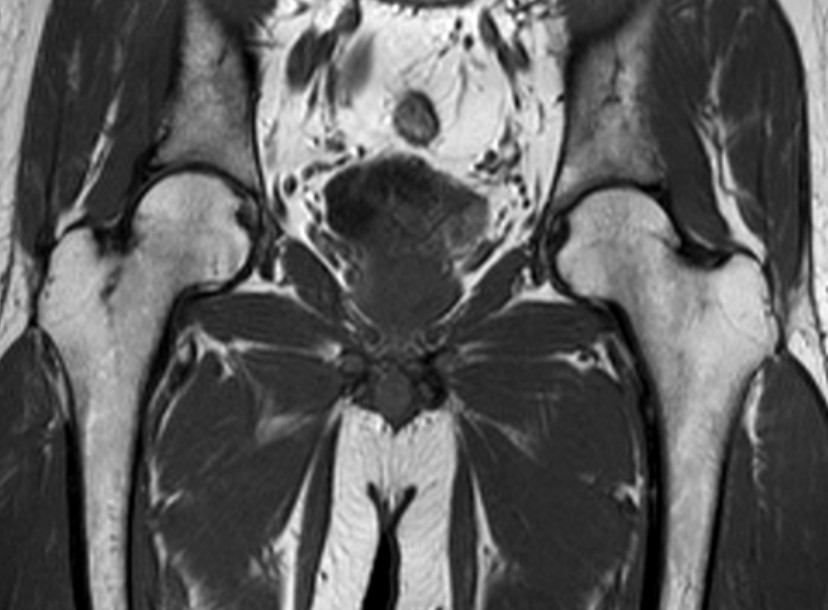

髋关节-fs T2

髋关节-T1